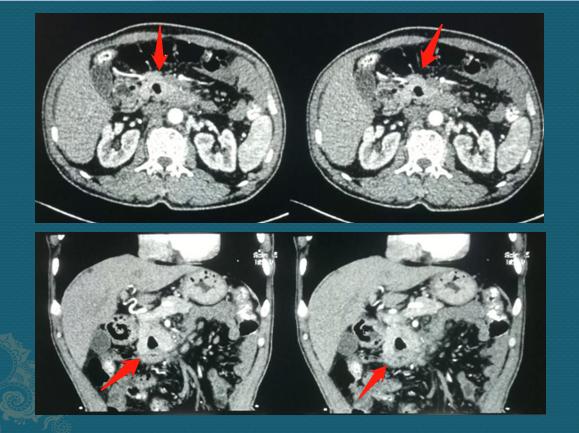

这位病人59岁,因为胃胀和上腹痛半个月做钡餐检查,发现十二指肠下段梗阻,有一个半圆形的充盈缺损(箭头),进一步胃镜检查确诊为十二指肠腺癌,增强CT观察周围结构,没有肝脏转移和周围侵犯,具备手术条件:

这位病人在3年前已经成功手术切除,今年复查情况挺好的,体重恢复,也没有贫血。